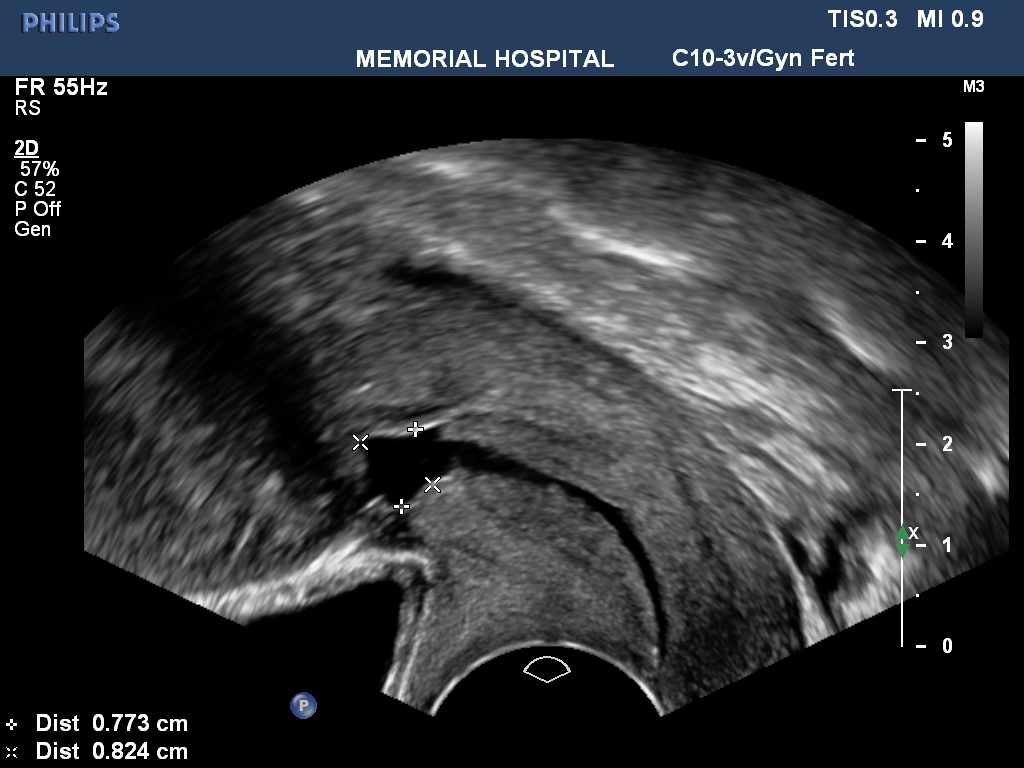

İstmosele bağlı şikayetleri olan hastalarda yapılan görüntileme yöntemleri ile istmosel tanısı kesinleştirilir. Görüntüleme yöntemlerinin başında ultrasonografi vardır. Özellikle transvajinal yolla yapılan ultrasonografide yüksek doğrulukta tanı konabilmektedir.